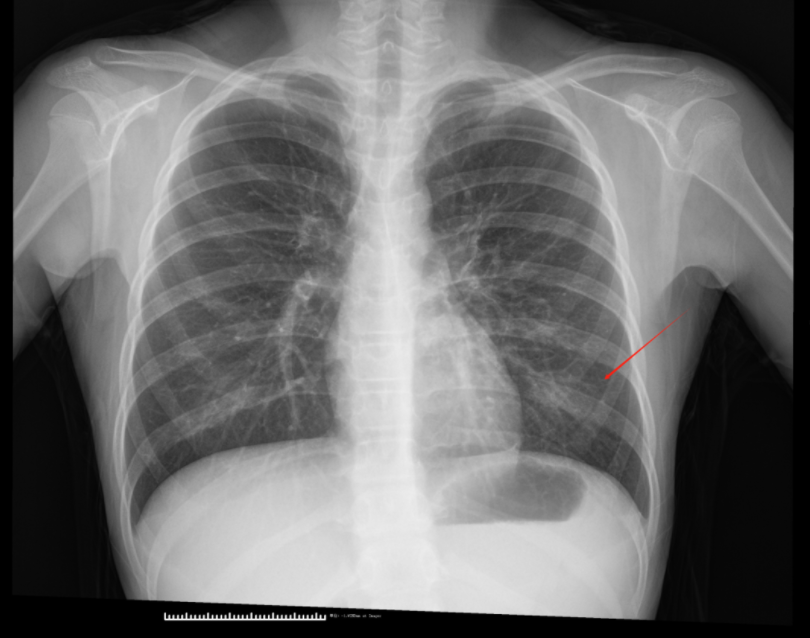

胸部DR

上图是一位10岁的小患者,分别进行了胸部DR和CT检查。DR仅显示左肺下叶纹理增多、模糊,而CT显示左肺下叶大片絮状稍高密度影,对病变的范围和程度较DR更为直观和清晰。